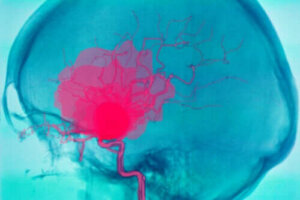

Krwotok śródmózgowy to poważne schorzenie, które może narażać pacjenta na utratę życia. Polega na krwawieniu wewnątrz mózgu. Z tego powodu inne części ciała zostają pozbawione tlenu.

Krwotok śródmózgowy, jak wspomnieliśmy już we wstępie, to krwawienie, które pojawia się wewnątrz mózgu. Zazwyczaj wywołuje nagły rozwój niedoborów neurologicznych, a nawet śpiączkę.

Dzieje się tak z powodu braku dopływu krwi do innych części mózgu, ponieważ krew nie jest w stanie kontynuować swojej podróży przez naczynia krwionośne. Należy odróżnić krwotok śródczaszkowy od krwotoku śródmózgowego.